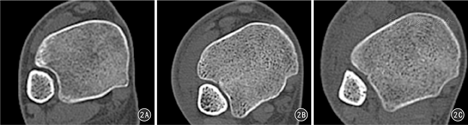

(1)下胫腓联合形态的分型:选取每例患者水平位CT平扫数据,选取距离胫距关节面9~11 mm的CT扫描图像进行影像学分析。根据腓骨在胫骨下端所形成的曲度,将其分为半圆形、新月形和矩形三种形态。(2)胫腓骨中心距离测量[9]:选取距离胫距关节面9~11 mm的CT平扫图像进行参数测量。首先,在下胫腓联合平面作切线a,然后平行于该线分别作腓骨和胫骨内外侧边缘的切线,垂直于切线a作胫骨及腓骨前后缘切线,从而形成两个包绕胫骨和腓骨的四边形;最后,连接两个四边形的对角线,其交叉点分别为腓骨及胫骨的中心,测量胫骨中心至腓骨中心的距离。(3)胫腓骨间隙宽度测量[9]:平行于切线a分别作腓骨内侧缘及下胫腓联合内侧缘的切线b和c,测量两线之间的垂直距离。(4)胫腓骨前缘距离测量[9]:测量胫骨前缘切线及腓骨前缘切线之间的垂直距离d。见图1。

45例下胫腓联合CT影像显示形态有3种,其中半圆形14例(31.11%),男3例,女11例;新月形15例(33.33%),男6例,女9例;矩形16例(65.56%),男7例,女9例。见图2、图3。